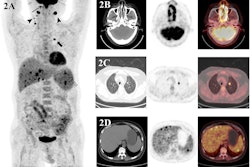

A 49-year-old patient with primary clinical stage III melanoma underwent F-18 FDG-PET. The primary tumor Breslow thickness was 6.5 mm. On initial F-18 FDG-PET images, this patient had a high SUVmax (52), resulting in limited survival with the occurrence of brain metastasis in the first year of follow-up (horizontal arrow). Notably, during the course of the treatment, the patient underwent surgical removal of the primary tumor as well as lymph node dissection, followed by neoadjuvant radiotherapy and immunotherapy. Image courtesy of Cancers.